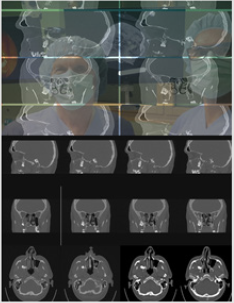

Figure 4: Telemed discussion about follicular cyst which heads out of the lateral wall of the maxillary sinus, with navigation through the frames in medical datasets in real time.

An adult male patient, Caucasian, NM, 57 years old with test results suspecting of a follicular cyst which spreads out to the lateral wall of the maxillary sinus (Figure 4). The cyst was discovered during a routine radiology exam (MSCT nose/sinuses). It is big in size and is causing a deformity of the lateral wall of the maxillary sinus. These kinds of cysts are usually asymptomatic, but with the presence of a potential infection, the patient responds with pain on palpation of the lateral wall of the maxillary sinus (typical somato-senzoric feeling of pain to pressure, touch, vibrations etc.). Our patient, who with earlier mentioned test results also had an obstruction of the nasolacrimal ductus, has adduced a similar kind of pain and headache.

It has been known that odontogenic cysts are of characteristic appearance and that they never penetrate the maxillary sinus, but rather, with their growth, move sinus walls and compromise him in that way. Radicular cysts are the ones to be diagnosed most often because they can raise the bottom of the maxillary sinus itself, while keratocysts and follicular cysts are rarely diagnosed. They can deform the posterior and lateral walls of maxillary sinuses while creating an image like duplicator of the sinus. They are usually created after the making of a calcified crown bound to wisdom teeth – like it was with our patient (tooth in permanent dentition /18), but they can also be corelated with canine teeth as well as with other premolars of the upper jaw. They’re usually showed radiologically as ‘’unilocular lighting with the crown and the root of mentioned tooth’’. In case of persisting inflammation (chronic inflammation) ameloblastoma can occur from bigger cysts with possible future growth of mucoepidermoid carcinoma as well as plate cells carcinoma. A follicular cyst can cause pathological jaw fractures.

It is well known that the pathology of the maxillary sinus of odontogenic origin is extremely important in rhinology, primarily because of close anatomical contact between the roots of upper teeth which can, in an inflammatory process, cause a sinus inflammation. With parodontitis and odontogenic cysts, iatrogenic factors are a relatively often cause of maxillary sinus inflammations and they occur after tooth treatment. Oroantral communication with the associated fistula presents the leading iatrogenic cause, and it occurs by tooth extraction which is an everyday procedure in dental clinics. Therefore, with extra attention from dentists (a positive Valsalvin test), every oroantral communication can be sanated and with that it won’t, with a chronic inflammation, come to forming an oroantral fistula.

Therapeutical approach: It should be emphasized that there isn’t a possibility of preventing the emergence of follicular cysts of maxillary sinus. Therapy is primarily based on the need of sanating the cause of the inflammation and then the application of the antibiotics. After that comes treating the sinus itself with usage of appropriate surgical methods. Of course, it should be borne in mind that the inflammation of the maxillary sinus can occur spontaneously and the reduction and remodeling of the maxillary sinus can happen with the presence of odontogenic lesions. The choice itself of surgical treatment of the odontogenic lesions depends on their position as well as their size. In the case of our patient, NM, the choice of surgical treatment was intraoral enucleation of the lesion. It could have been done per viam with Caldwell-Luc’s type of operation through fossa canine or, as in our patients case, with the application of osteoplastic contactless surgery of the sinus with necessarily disposing of the tooth. Of course, it is more than necessary to fully remove all the pathological anthral tissue. The described contactless surgical approach is chosen because this form of pathological substratum cannot be sanated with the minimally invasive approach and/or with medication therapy.